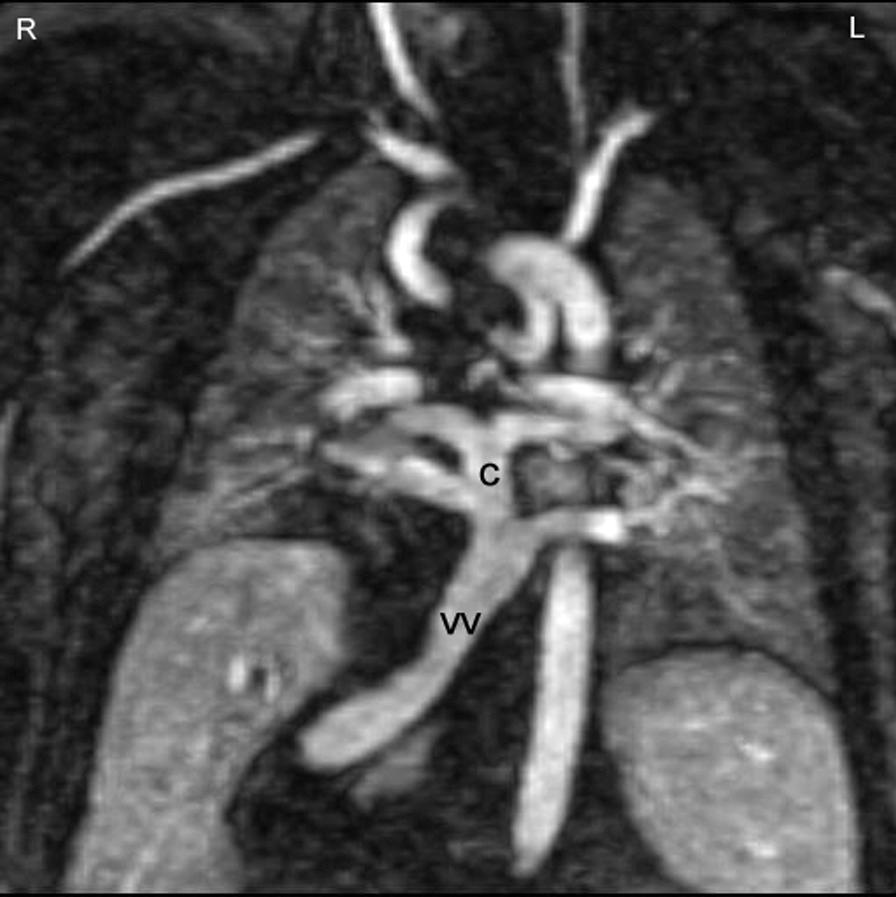

Cardiovascular magnetic resonance (CMR) has been utilized in the management and care of pediatric patients for nearly 40 years. It has evolved to become an invaluable tool in the assessment of the littlest of hearts for diagnosis, pre-interventional management and follow-up care. Although mentioned in a number of consensus and guidelines documents, an up-to-date, large, stand-alone guidance work for the use of CMR in pediatric congenital 36 and acquired 35 heart disease endorsed by numerous Societies involved in the care of these children is lacking. This guidelines document outlines the use of CMR in this patient population for a significant number of heart lesions in this age group and although admittedly, is not an exhaustive treatment, it does deal with an expansive list of many common clinical issues encountered in daily practice.

心血管磁共振(CMR)在儿科患者的管理和护理中已经应用了近 40 年。它已经发展成为评估最小的心脏的宝贵工具,用于诊断、介入前管理和随访。尽管在许多共识和指南文件中提到,但在儿科先天性心脏病和后天性心脏病领域,目前还缺乏一份由众多参与儿童护理的学会共同认可的、最新的、独立的、针对 CMR 使用的大型指南。本指南文件概述了 CMR 在该年龄段的许多心脏病变中的应用,尽管不能说是详尽的治疗方法,但它确实涉及了在日常实践中经常遇到的许多常见临床问题的广泛列表。